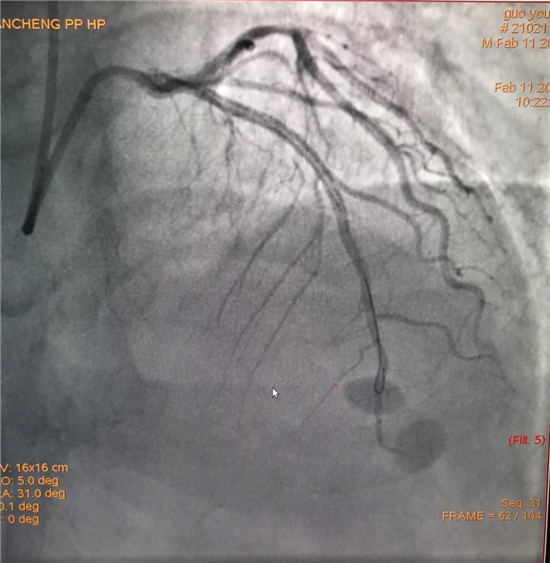

除夕,郭先生無明顯誘因突發(fā)胸痛,120急救人員到達(dá)現(xiàn)場,心電圖顯示:竇性心律完全性束支傳導(dǎo)阻滯。信息立刻發(fā)送到胸痛中心介入微信群中,心內(nèi)科值班醫(yī)生初步診斷為急性廣泛前壁心肌梗死,必須盡快進(jìn)行急診支架治療,開通血管。值班醫(yī)生電話指導(dǎo)院前治療,并立即啟動胸痛綠色通道,24小時備班的介入治療團(tuán)隊(duì)立即到位,9:30患者被送到導(dǎo)管室行冠脈介入診療,9:40急診PCI手術(shù)隨之開始,冠脈造影檢查提示左前降支閉塞,植入支架,堵塞的血管被順利打通,患者癥狀緩解,手術(shù)非常成功,10:20患者被送往病房進(jìn)一步治療。